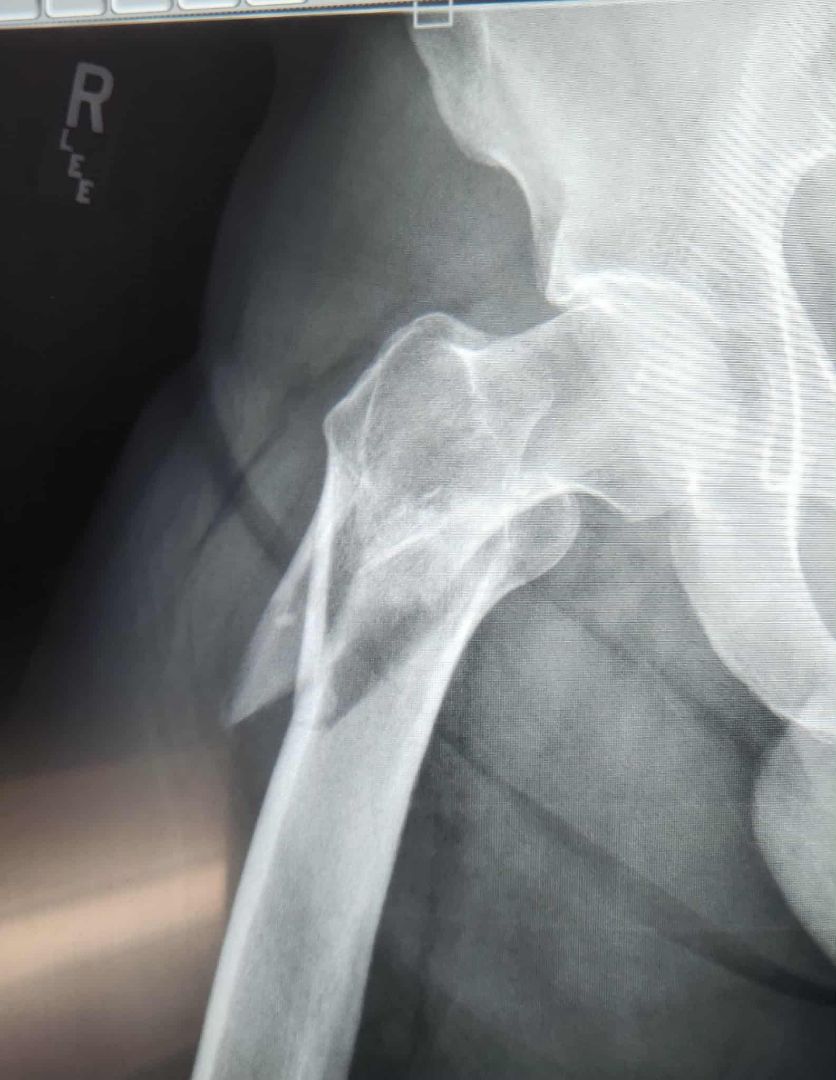

My brother-in-law… age 60 years, healthy, scuba diver - swimmer for a living… fell last night on the grass and broke his femur.

Makes me wonder what his bone density was before the fall. A pretty well-built man. Muscled… no fat.

He’s not the kind of guy that would check such a thing as bone density. So, probably not doing any bone density supplements. Now has a titanium rod.

A bit late…, but I suggested a DEXA bone scan. Good to know.